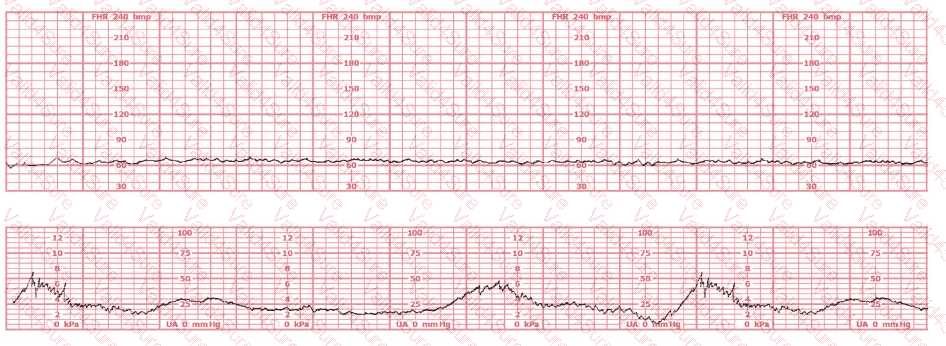

The fetal heart rate tracing shown is obtained upon the woman's admission to labor and delivery. This tracing is most consistent with what maternal condition?